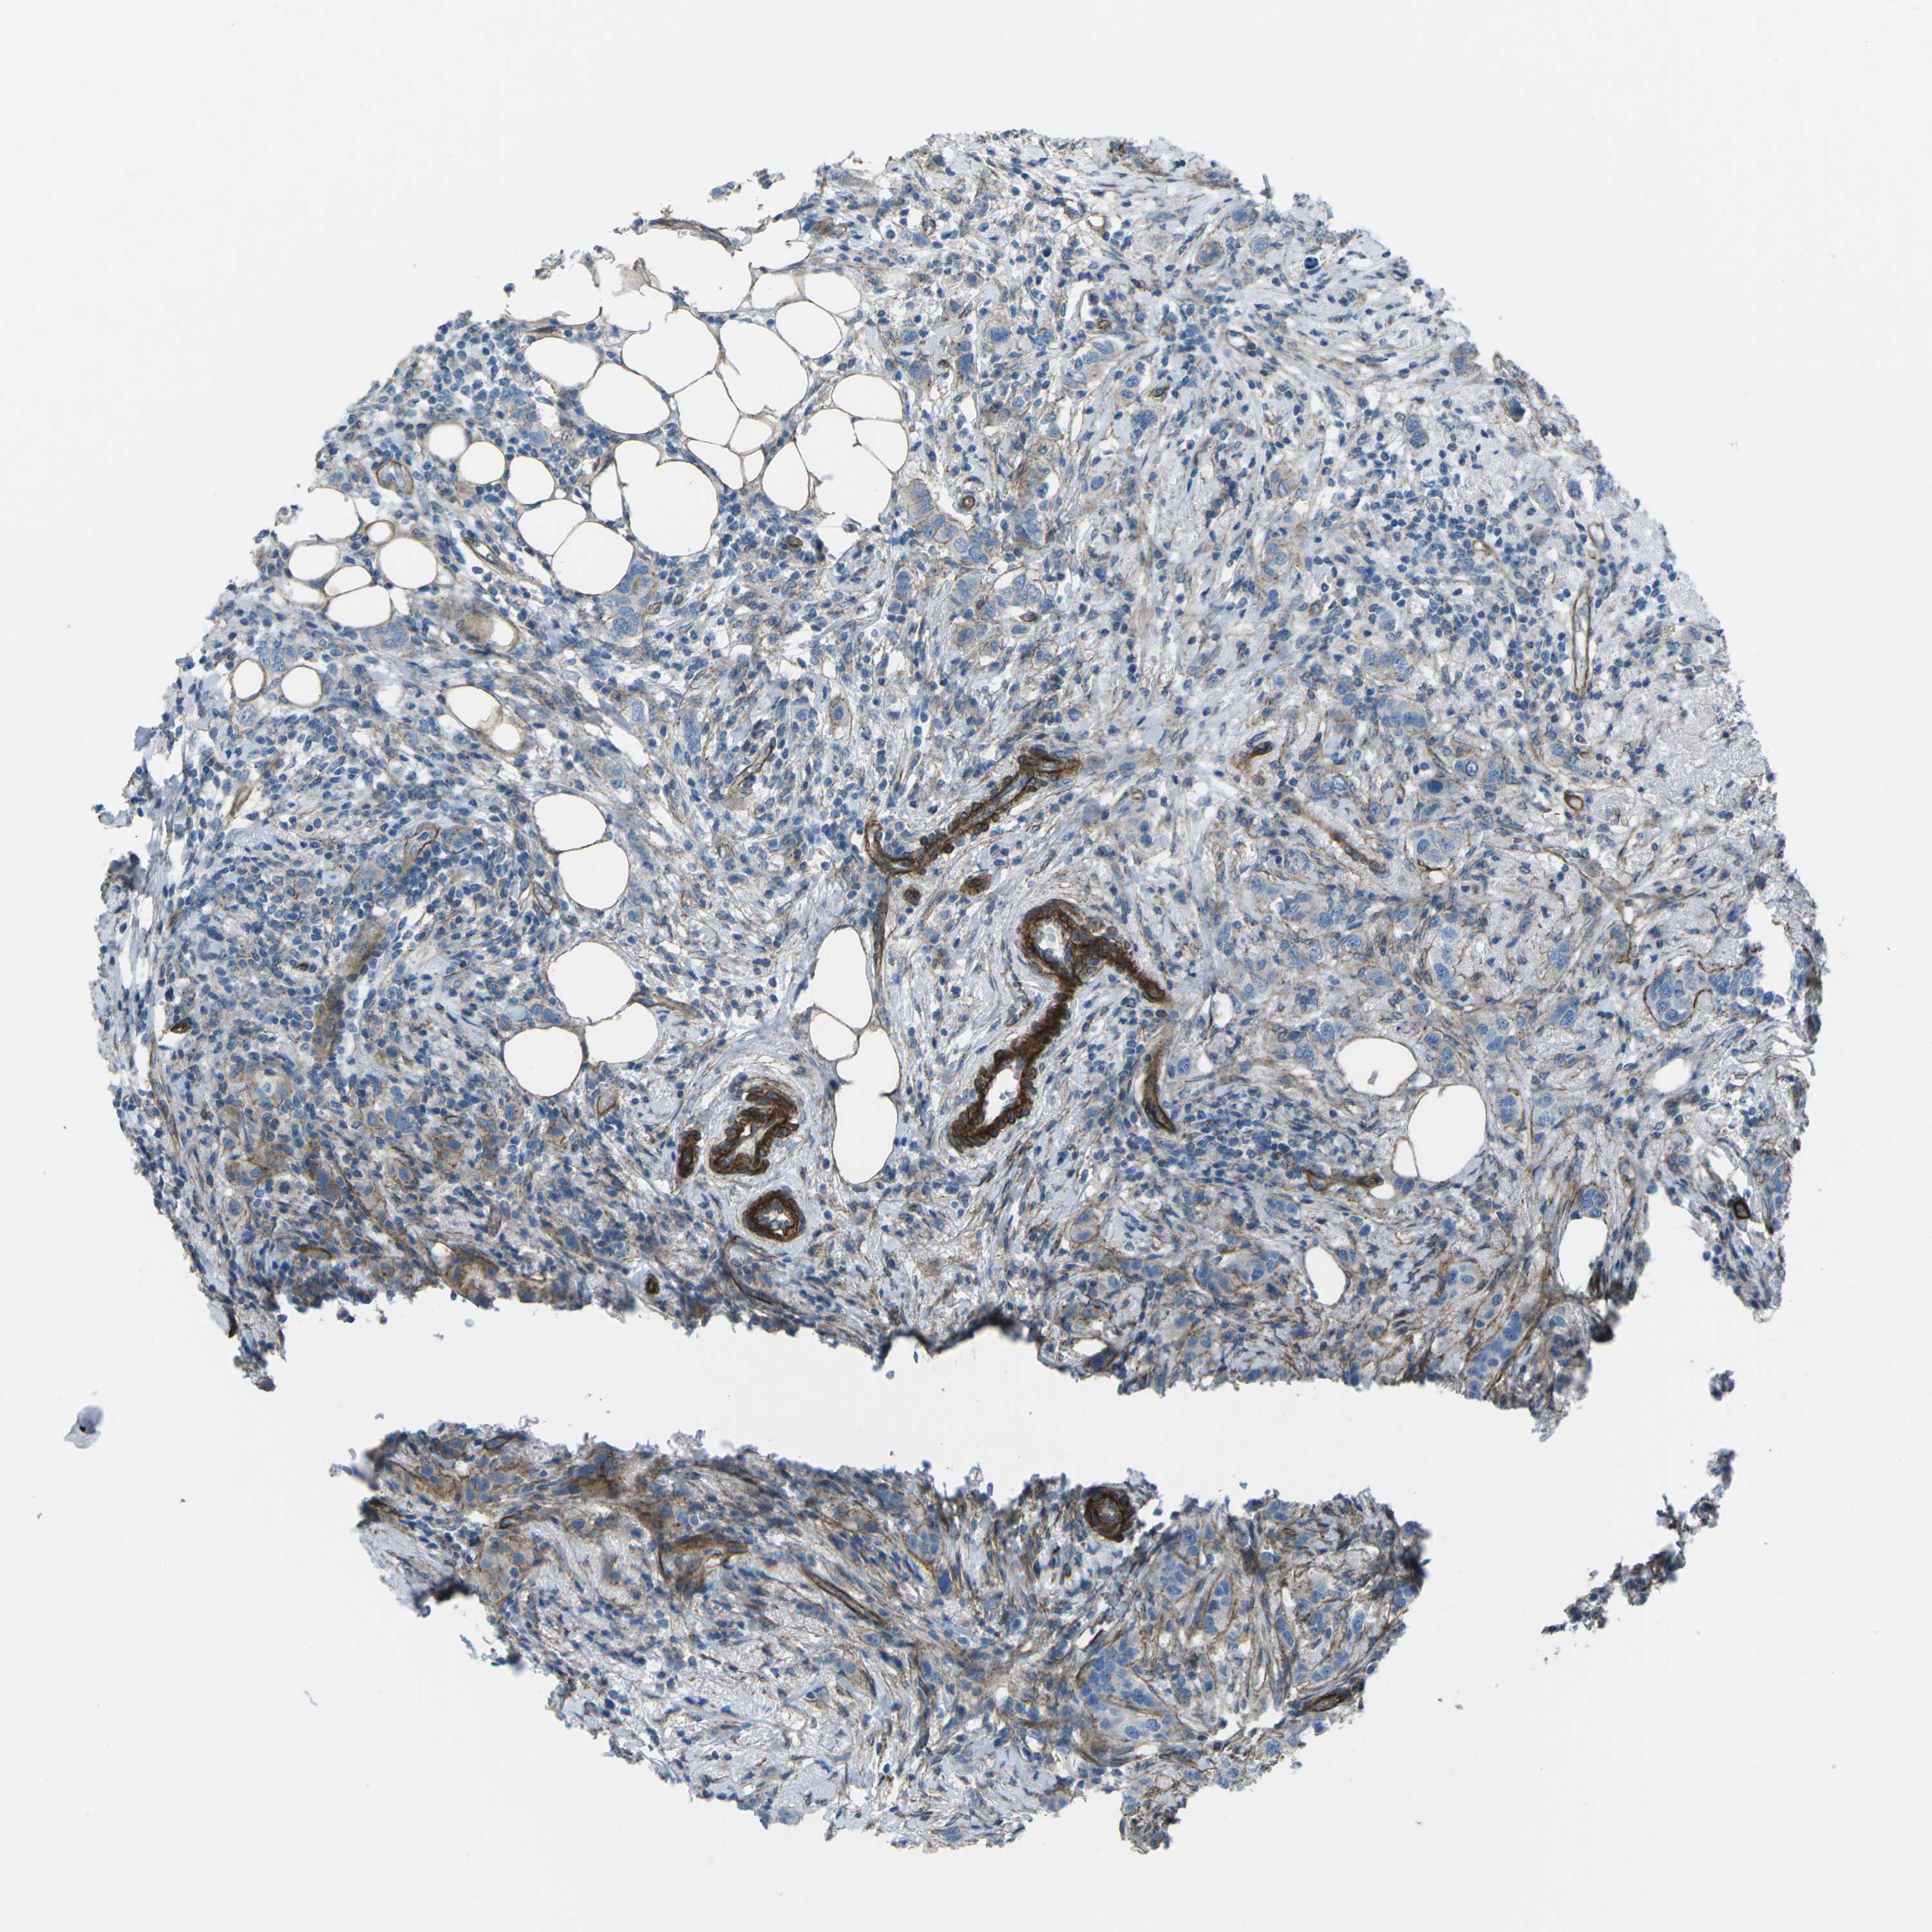

BRCA TCGA BRCA VALIDATION PROTEIN EXPRESSION

ANTIBODIES

AND

VALIDATION